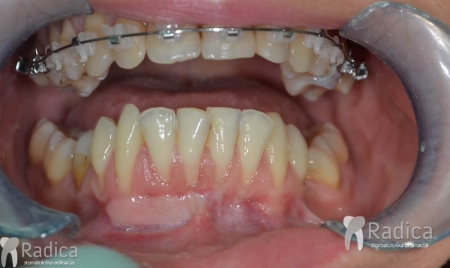

U ovom slučaju je 41.godinu starom pacijentu počeo nicati impaktirani desni gornji očnjak pri čemu je ugrozio lateralni sjekutić. Pacijentu je stavljen fiksni aparat te je zub smješten u luk. Kako je pacijent odustao od postave aparata u donjoj čeljusti na kraju nije dobivena zadovoljavajuća okluzija na što je upozoren.